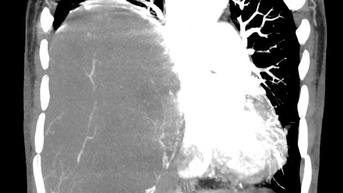

Phim chụp CT ổ bụng của bệnh nhân.

Chẩn đoán hình ảnh (CT ổ bụng có thuốc cản quang) cho thấy khối choán chỗ sau phúc mạc, kích thước 28 × 15 cm, cấu trúc hỗn hợp tổ chức mỡ – đặc , đè đẩy tạng trong ổ bụng nhưng không có dấu hiệu xâm lấn các tạng lân cận. Kết hợp lâm sàng và hình ảnh học, bệnh nhân được chẩn đoán sarcoma mỡ sau phúc mạc.